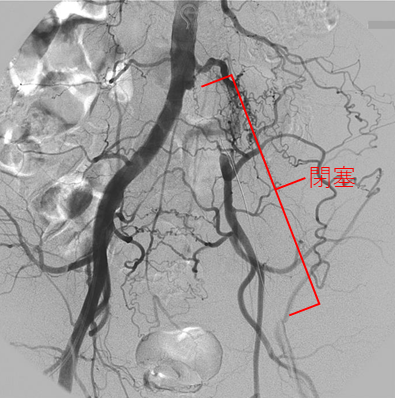

下肢閉塞性動脈硬化症は、動脈硬化が原因で下肢の動脈が細くなったり詰まったりする病気です。血流が不足して、足の冷感、歩行時の痛み、より重症化すると安静時の痛み、足の潰瘍・壊疽などの症状が現れます。

治療法としては、生活習慣の改善や薬物運動療法の他、血行再建術(血管内治療と外科手術)があります。血管内治療は外科手術よりも体に負担の少ない治療です。